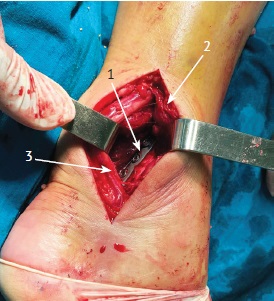

Рис. 2. Интраоперационная фотография выполненного заднемедиального доступа на этапе фиксации заднего края ББК 1/3-трубчатой пластиной:

1 — 1/3-трубчатая пластина, фиксирующая задний фрагмент ББК;

2 — задняя большеберцовая мышца, длинный сгибатель пальцев, отведенные крючком типа Фарабеф;

3 — длинный сгибатель большого пальца и задний сосудисто-нервный пучок, отведенные крючком типа Фарабеф

Fig. 2. Intraoperative photo of the performed posteromedial approach at the stage of fixation of the posterior edge of the tibia with a 1/3-tubular plate:

1 — 1/3-tubular plate fixing the posterior fragment of the tibia;

2 — posterior tibial muscle, flexor digitorum longus, retracted by the Farabeuf hook;

3 — the flexor hallucis longus and the posterior neurovascular bundle, retracted by the Farabeuf hook